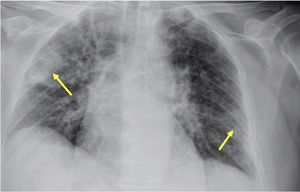

Durante su estancia en UCI, presentó mala evolución respiratoria con progresión radiológica y desarrollo de cavitaciones (fig. 2). Se añadió al tratamiento anfotericina B liposomal y se realizó broncoscopia con lavado broncoalveolar. La determinación de β-glucano en las muestras del lavado fue positiva y en el cultivo del BAL en agar Sabouraud se observó el crecimiento de colonias sugestivas de corresponder a 2tipos de hongos filamentosos distintos (fig. 3), que se identificaron por espectrometría de masas (MALDI-TOF) como Aspergillus fumigatus y Aspergillus terreus. El antifungigrama de ambas especies presentó un fenotipo salvaje, sin encontrar resistencias adquiridas; la cepa de A. fumigatus era resistente a fluconazol y la de A. terreus a fluconazol y a anfotericina B liposomal. Ambas cepas resultaron sensibles a caspofungina, itraconazol, voriconazol, posaconazol, anidulafungina, micafungina e isavuconazol.